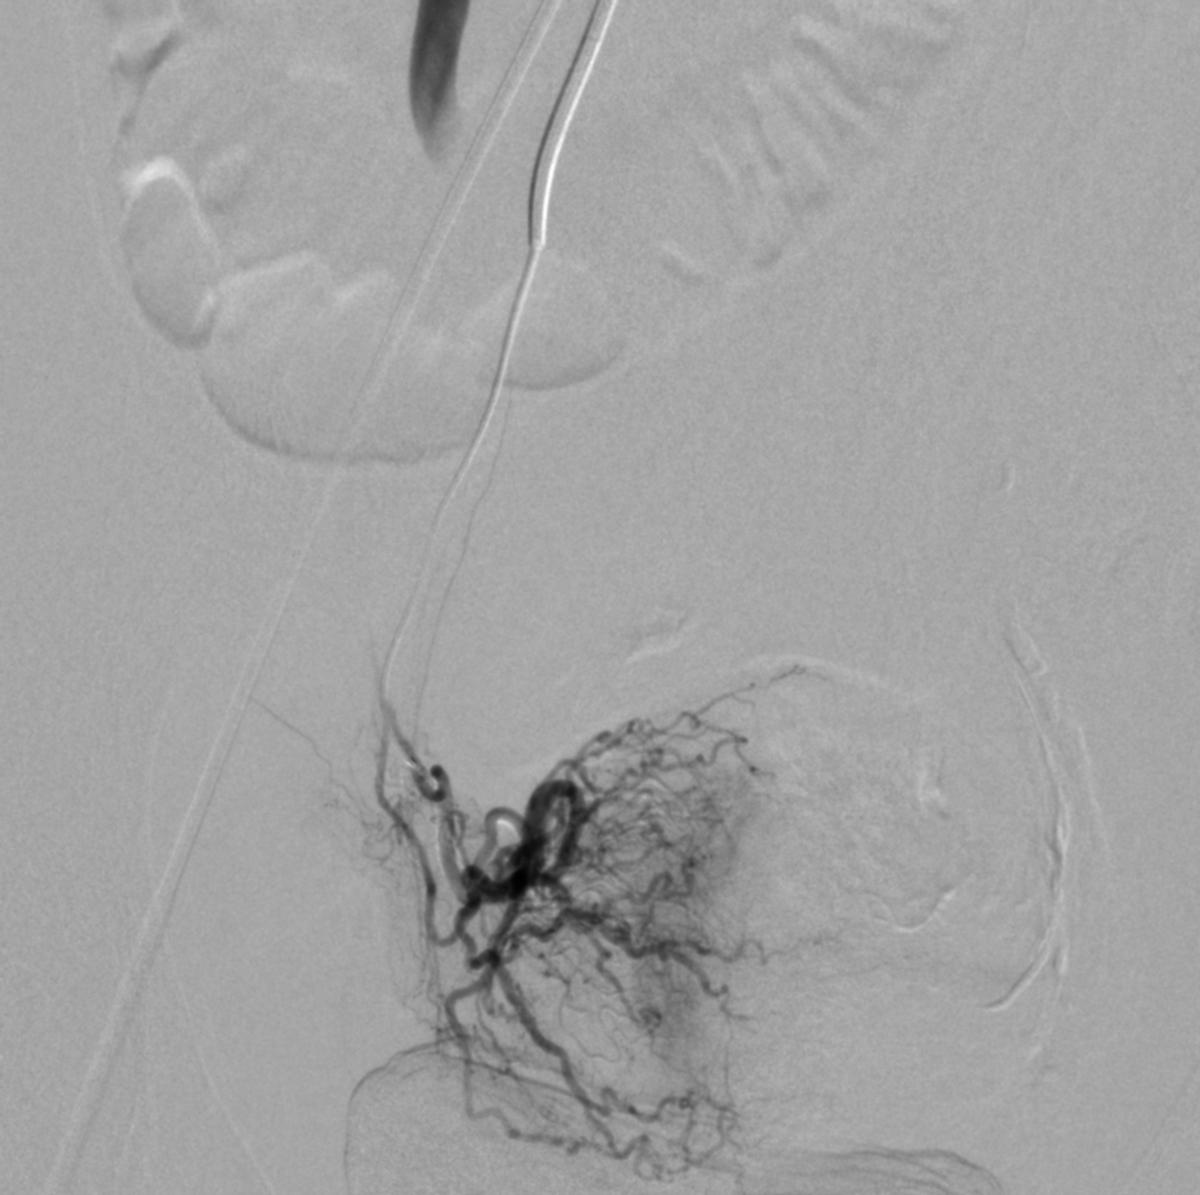

患儿完成入院前术前检查,并进行了全科的术前讨论。结合患儿体征及相关的术前检查,目*考前**虑PROS综合症。目前主要解决的是月经出血的问题,可以通过栓塞双侧子宫动脉来进行治疗。患儿全麻后,使用5F穿刺针行右股动脉穿刺,成功后置入5F血管鞘,导丝引导下置入5F Headhunter Angiopointer造影导管,在导丝引导下选入髂内动脉,进入子宫动脉,造影见左侧子宫动脉远端纤细,右侧子宫动脉螺旋增粗,微导丝引入微导管进入子宫动脉,使用聚乙烯醇颗粒栓塞剂350um-560um,栓塞微粒球(300-500um)分别行双侧子宫动脉栓塞,栓塞后造影未见子宫动脉远端分支显影。

栓塞治疗

微导管栓塞治疗